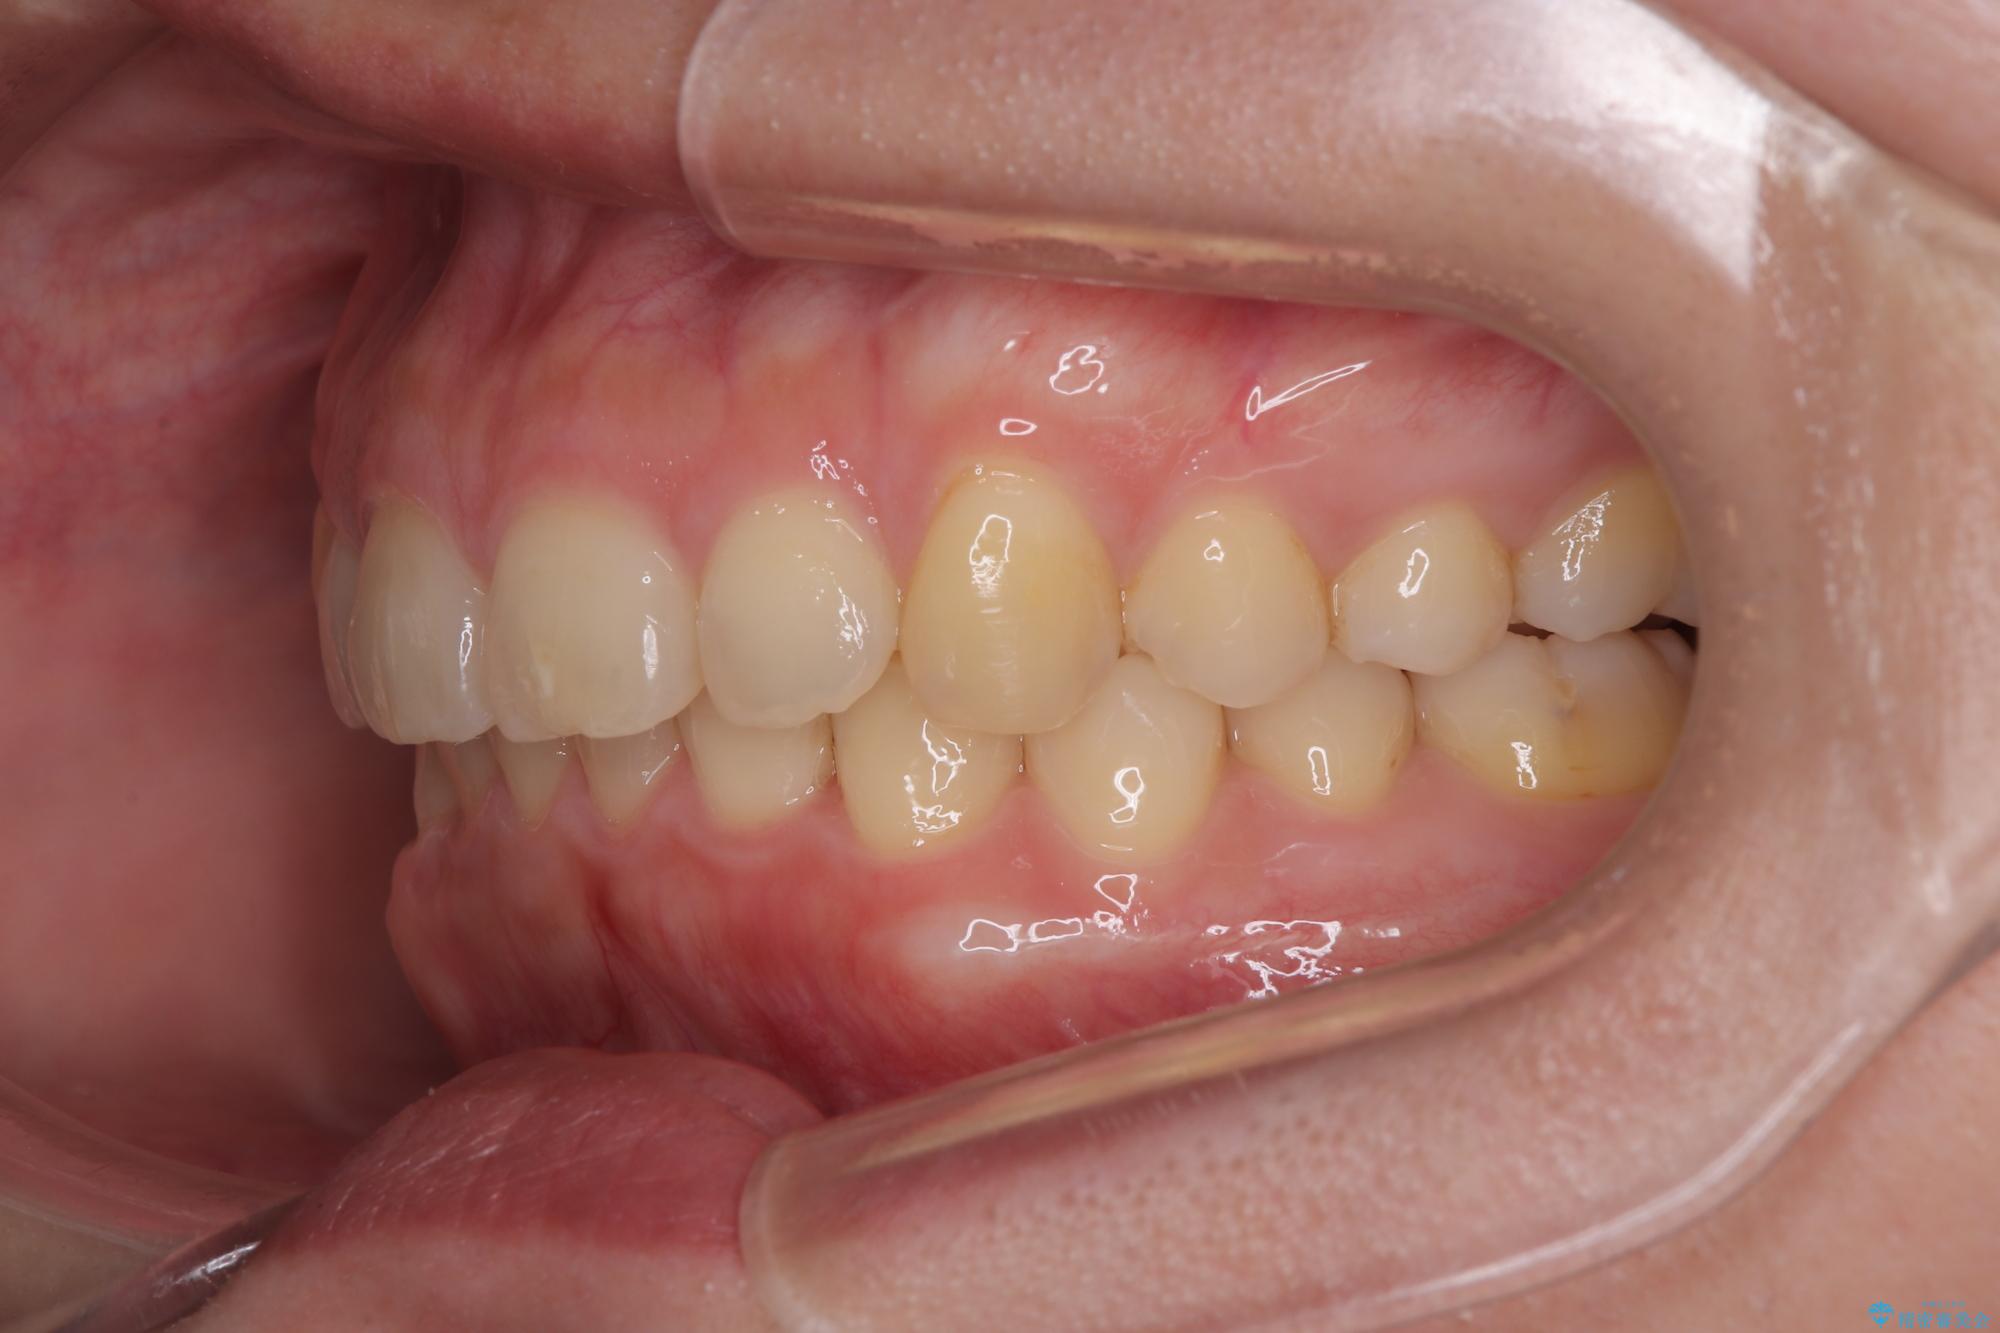

隠れた前歯が気になる ディープバイトのワイヤー矯正治療

- 下顎前歯が完全に隠れてしまっていることを気にして来院された患者様です。

下顎の臼歯が手前に傾斜していることで咬み合わせが深くなってしまい、下顎前歯が見えないほどに上顎前歯が覆い被さっている状態でした。

下顎臼歯を起き上がらせるためにユーティリティーアーチを使用し、一気に深い咬み合わせを改善することができました。